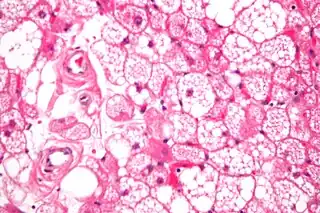

Hibernoma (aumento intermedio).